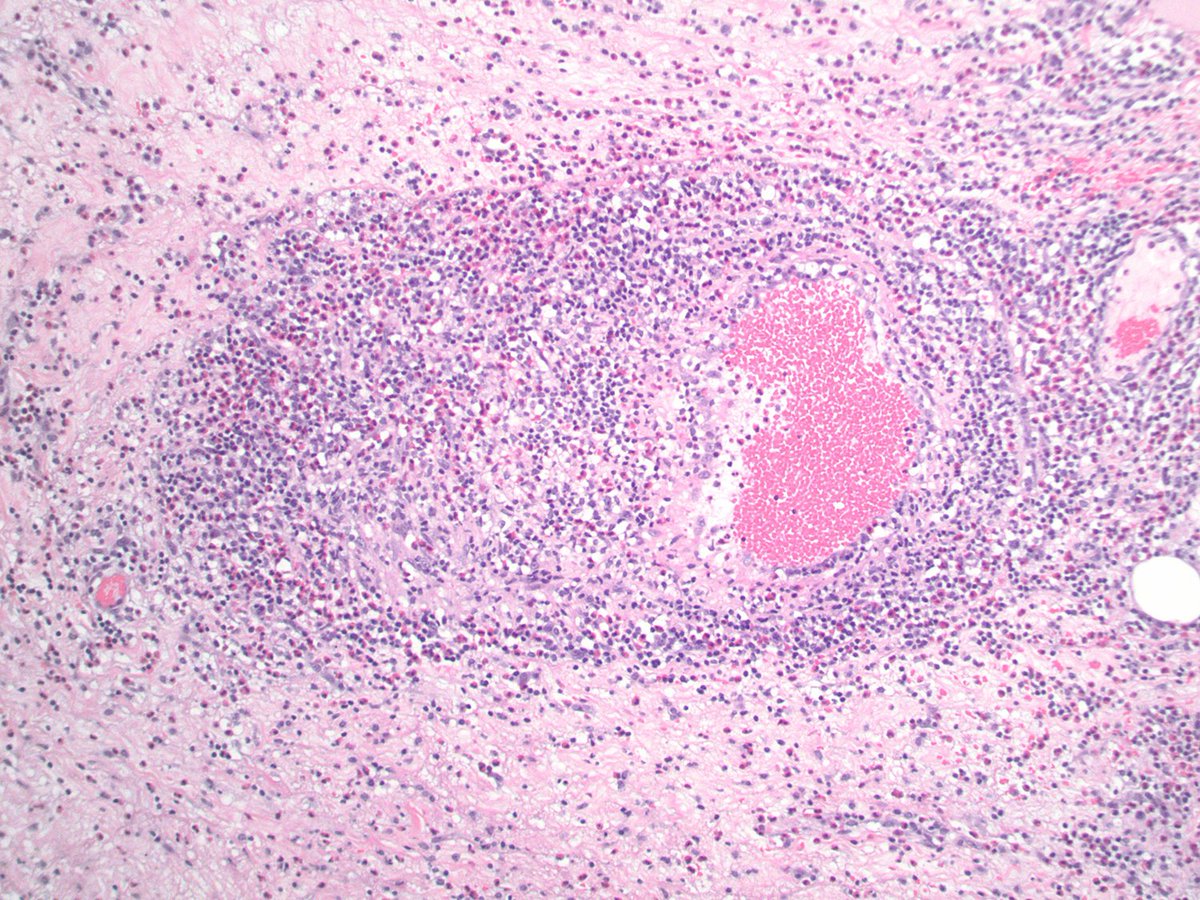

Let's work through a case together! Young adult with hemispheric brain mass with post-contrast enhancement.

1. What is your histologic diagnosis

2. What IHC and/or molecular tests should we consider when we see this specific histopathology?